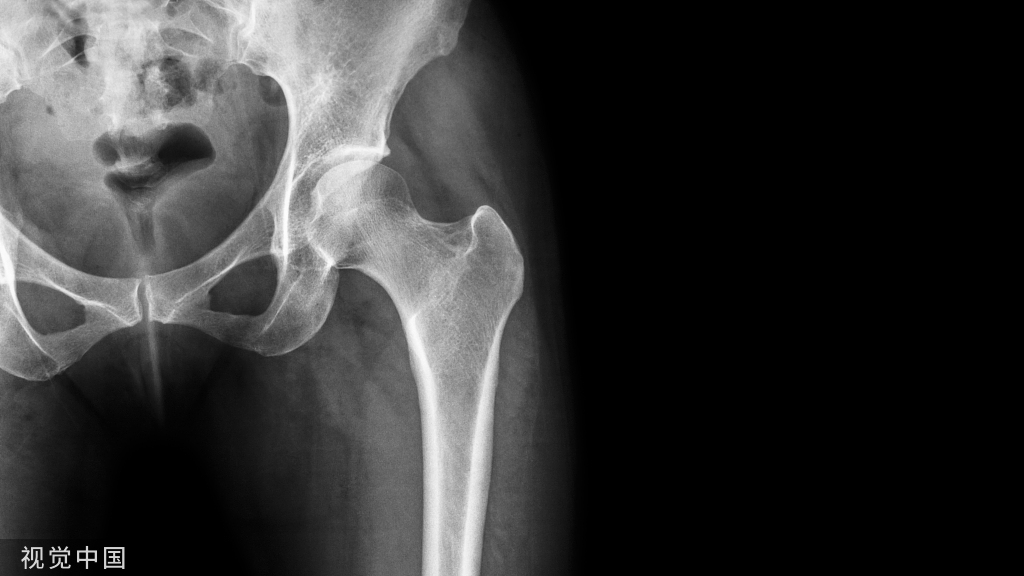

图示MRI:初诊(A)、8个月(B)和18个月(C)

患者女,30岁,腰痛伴双下肢疼痛,无马尾受压症状。查体示:L4/L5和L5/S1双侧棘突压痛放射至双下肢,左侧、右侧直腿抬高试验50°(+)。双下肢皮肤感觉、肌力正常。图示:L4/L5椎间盘突出后再吸收,L5/S1椎间盘前后无变化。腰椎间盘突出后重吸收:是指腰椎间盘突出症患者未经手术治疗而发生的突出髓核消失或缩小的现象。对腰椎间盘突出后重吸收现象的研究,最早可以追溯到1984年,国外学者Guinto通过个案报道分享了一例腰椎间盘突出症患者保守治疗CT随访案例,首次发现突出的椎间盘组织可以缩小或者消失,并称之为“自发性消退”。